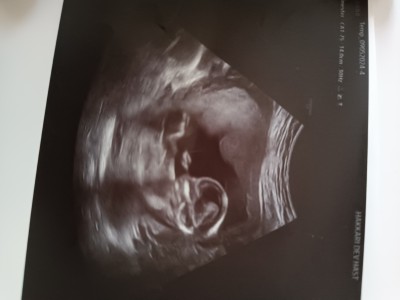

Kizlar bir tahmin alabilir miyim. Kendini göstermedi

Gebelik haftası 14+3